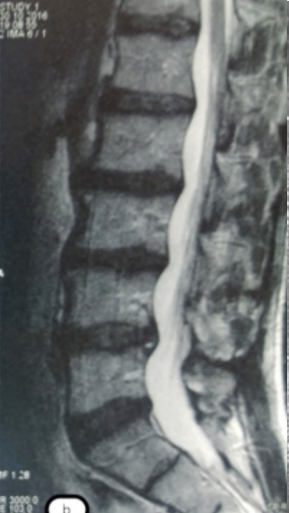

Грыжа Диска L4-L5

3 процедуры ФДТ, 9 процедур MBST

Параметры изменяются в зависимости от процедуры

Дата публикации: 22.08.2025 14:27:20

Спондилодисцит L3 – L4

4 процедуры ФДТ, 9 процедур MBST, 20 процедур ИПМТ

Дата публикации: 22.08.2025 14:27:12